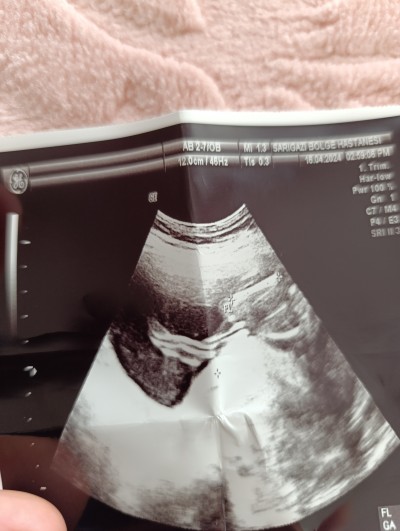

Bilgisini olan yazarmi

Hiiiic anlamam kuzum ama erkek geçti içimden.

Sağlıkla al kucağına insallah ♥️